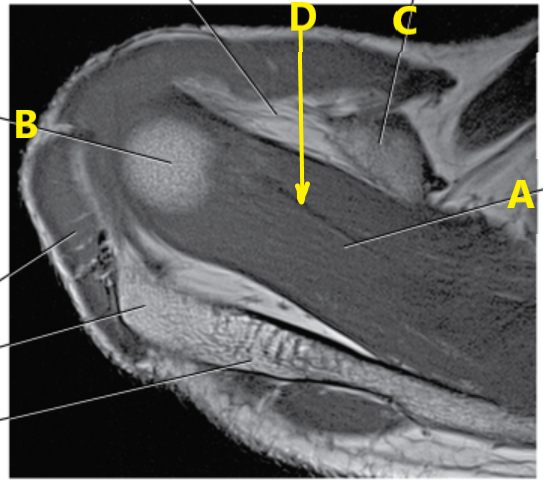

What is D ?

supraspinatus tendon

glenoid labrum

acromion process

What is b ?

supraspinatus muscle